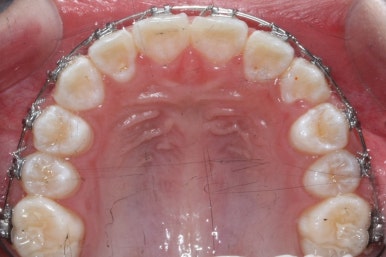

영구치도 이제 거의 다 나왔고 삐뚤한 다른 부분도 전체 메탈장치를 붙였습니다.

장치는 윗니부터 붙였습니다.

입안에 장치가 있다보니 불편할 수 있는데요. 이물감을 최소화 하고자 이동을 해야 할 양이 적은 아랫니들은 천천히 장치를 붙이기로 했습니다.

아래쪽에도 이제 장치를 전부 부착했습니다.

한 쪽의 송곳니는 제위치로 벌써 자리를 잡았네요.

장치를 부착한 후에 순차적으로 변화가 나타나는 모습입니다.

총 4장의 사진 동안 경과한 시간은 불과 6개월 입니다. 헤드기어를 통해 사전에 작업을 해뒀기 때문에 이후 연산동덧니교정 과정은 편해진 것이죠.

윗니만 6개월이 지난 모습입니다.

치열이 매우 가지런해졌죠. 이 후에는 특이사항 없이 종료가 되었습니다.